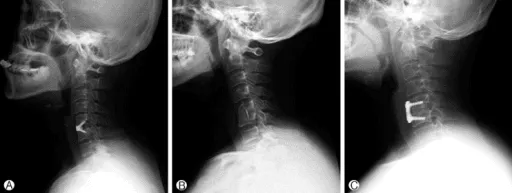

X-Ray

An X-ray provides rapid images of the bony structures of the cervical spine. It can reveal narrowed disc spaces, fractures, bone spurs, and changes consistent with osteoarthritis. X-rays do not show soft tissue structures like discs or nerves.

Xray image of a neck with a metal cage placed during ACDF surgery.

Traditional Fusion Surgery (ACDF)

Anterior cervical discectomy and fusion (ACDF) has been the standard surgical treatment for cervical disc herniation for decades. The procedure involves removing the damaged disc, relieving pressure on the affected nerve or spinal cord, and then permanently fusing the adjacent vertebrae using bone graft and metal hardware. While effective for many patients, fusion permanently limits the neck’s natural range of motion and transfers mechanical stress to adjacent spinal levels. Research has shown that adjacent segment disease requiring reoperation affects approximately 11% of fusion patients, and radiographic degeneration at adjacent levels develops in up to 30%.

An xray highlighting the ACDF on the Cervical spine.